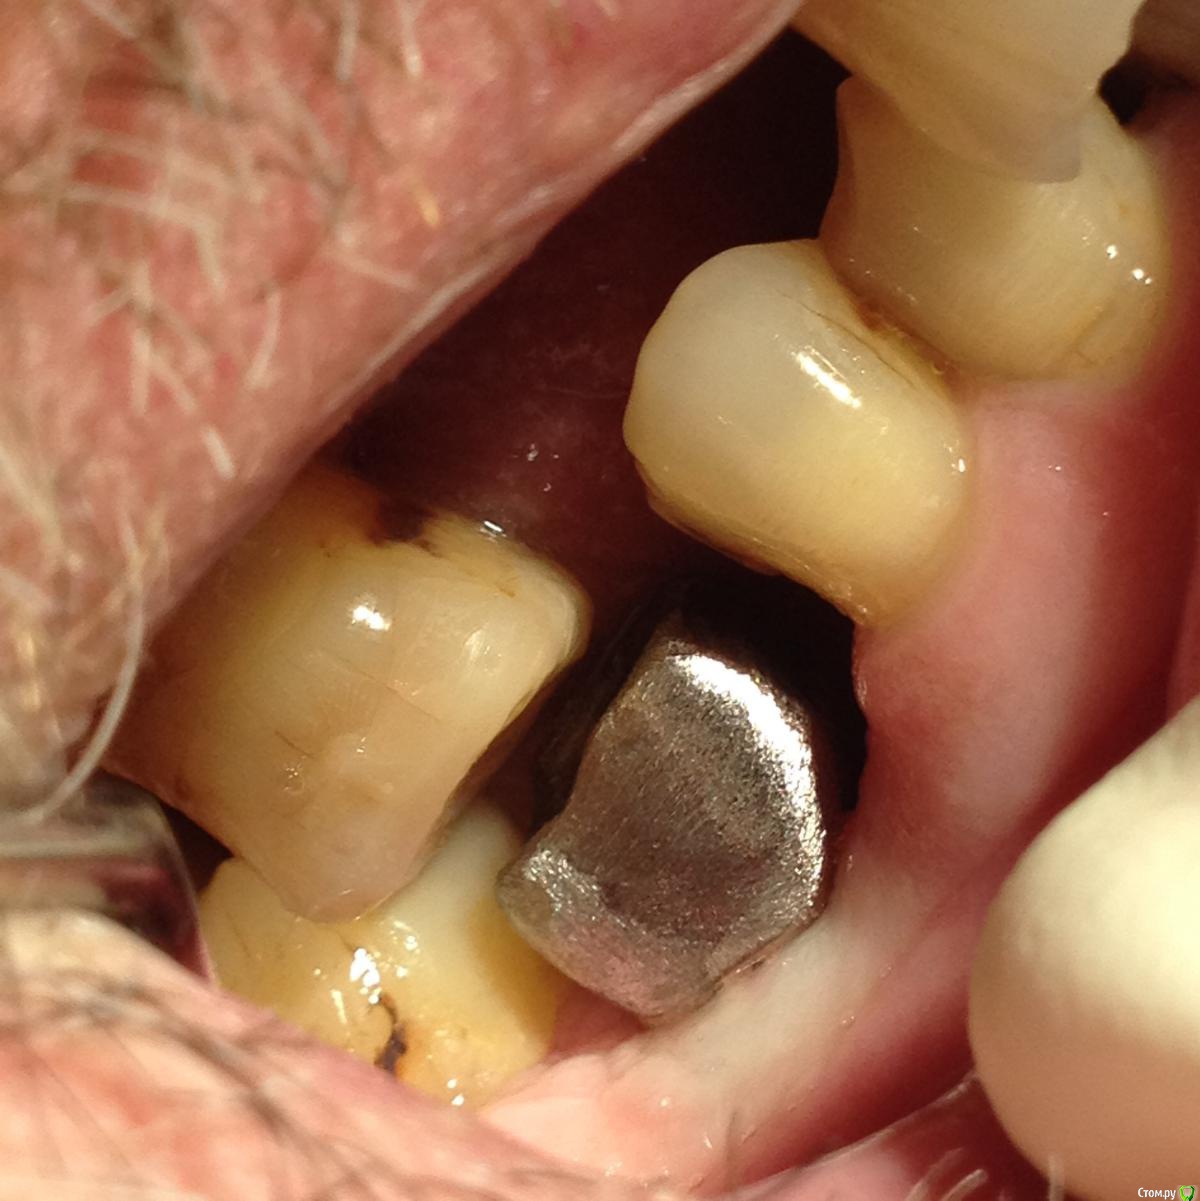

Shakirbura Опубликовано 13 марта, 2016 Поделиться Опубликовано 13 марта, 2016 Здравствуйте, коллеги! Собственно, моя первая работа на имплантатах. Очень хочется услышать мнение опытных врачей, сам еще плохо понимаю где есть ошибки. Сразу оговорюсь, что контакт между 46,45 исправлен.Заранее спасибо! Ссылка на комментарий

alekszander Опубликовано 14 марта, 2016 Поделиться Опубликовано 14 марта, 2016 Для первой работы не плохо, особенно если еще мало чего понимаете. Вопрос - зачем мост в 3-м сегменте? Ссылка на комментарий

Shakirbura Опубликовано 14 марта, 2016 Автор Поделиться Опубликовано 14 марта, 2016 Для первой работы не плохо, особенно если еще мало чего понимаете. Вопрос - зачем мост в 3-м сегменте?Мостом делал с расчетом уменьшить нагрузку. Встали как то не очеь хорошо импланты. Вы бы сделали одиночки в этой ситуации? Ссылка на комментарий

chervoncevdaniil Опубликовано 14 марта, 2016 Поделиться Опубликовано 14 марта, 2016 Мостом делал с расчетом уменьшить нагрузку. Встали как то не очеь хорошо импланты. Вы бы сделали одиночки в этой ситуации?все правильно,что импланты объединили в боковом сегменте Ссылка на комментарий

Freelancer1981 Опубликовано 14 марта, 2016 Поделиться Опубликовано 14 марта, 2016 тем более в такой ситуации обьединение продлит срок службы и вообще в боковых я страюсь почти всегда обьединять. Ссылка на комментарий

MaxDok Опубликовано 15 марта, 2016 Поделиться Опубликовано 15 марта, 2016 С гигиеной скорей всего будут проблемы . Ирригатор подарите пациенту ) Ссылка на комментарий